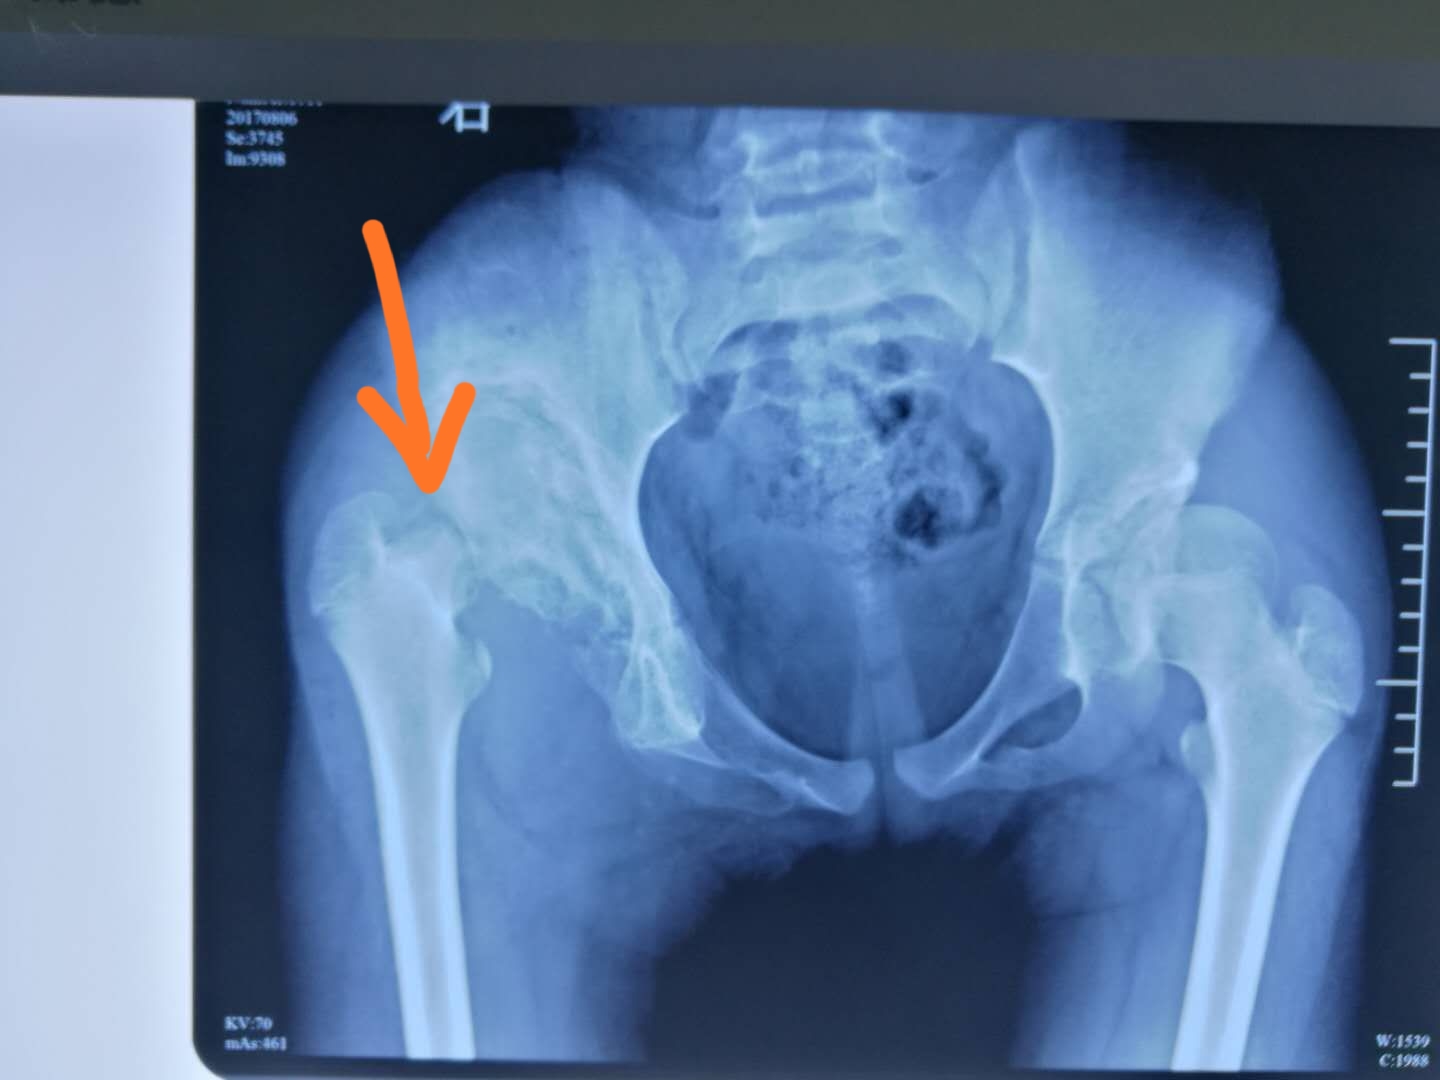

半年后拍片显示,右侧股骨头已经没有了

几年过去了,孩子的病情成了我心中始终放不下的牵挂……几天前,联系到了孩子的父母,了解孩子目前的状况。孩子母亲说,孩子今年15岁了,因为跟不上学校课程进度,加上行走不便,更怕出意外,现在已经辍学在家,跛行步态更加明显了,但臀部依然没有明显疼痛感,夏天到了,孩子早早地只能呆在空调间,因为怕热!为了给孩子看病,家里在镇上开了一间小吃店,我问孩子父母怎么打算呢?母亲说想争取多攒点钱,过两年再看看大医院里有没有好的医术给孩子做个手术,争取再读点书,唯一的期望是将来孩子长大成人后能过上普通人的生活,这是支撑她们一家人奋斗的动力。我安慰她,医学在发展,社会在进步,孩子一定会有治的,一定会有属于自己的美好的未来。